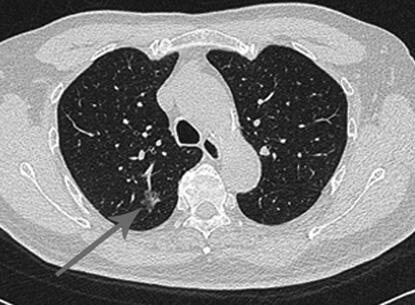

But now, recent scientific data has demonstrated that low-dose helical computed tomography (CT) scans may detect lung cancer at an earlier stage in high-risk patients, such as those who are or once were heavy smokers. This screening tool offers detection when the tumors are likely smaller and at a stage where more treatment options are likely available.

Historically, there have been no well accepted screening programs or blood tests for the early detection of lung cancer. Chest X-rays have been used in the past, but the smallest lung cancers detected are already between 0.2-0.4 inches in size when first found, or are only detected at a later stage of the disease.

According to Parker, the screening CT uses a very low-dose of radiation, requires no patient preparation, no IV, no contrast or dye material and is painless and fast. During the test, the CT scanner rotates around the patient, providing detailed images of the inside of their body. The patient will be asked to lie still on a table that passes through the center of the scanner for about seven to15 seconds. Then they are done. The radiation exposure is considered to be a fraction of what people are exposed to on a daily basis from natural background sources.